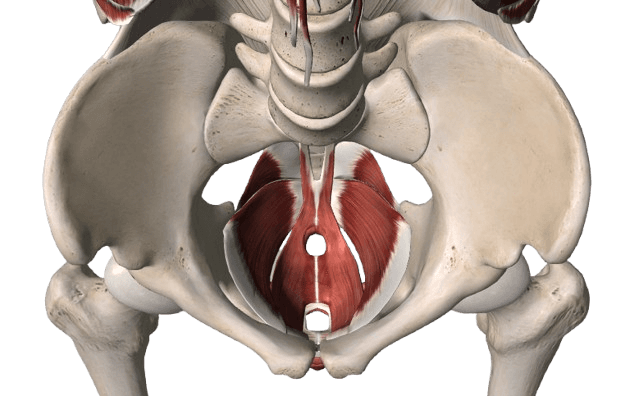

HMT (High Muscle Training) Non-invasive pelvic floor strengthening device inducing ~50,000 supramaximal contractions in 30 min via high-intensity electromagnetic field. Simply sit fully clothed for comfortable treatment.

UI-FIT An electromagnetic field-based device that aids rapid recovery from urinary incontinence and other conditions.

Pelvic Floor Muscle Training (PFMT) Training technique visualizing pelvic floor contraction on screen using biofeedback. Helps learn proper Kegel exercises for managing incontinence and laxity.

Surgical Correction for Incontinence Surgery inserting polypropylene mesh tape at mid-urethra via TVT or TOT to support the urethra. Over 90% success rate for stress urinary incontinence.

HMT-2000 Vaginal Pressure Measurement Diagnostic device measuring pelvic floor contractile strength in mmHg via internal sensor. Enables quantitative before/after comparison for treatment planning.

WP-3000 Vaginal Laxity Measurement Precision diagnostic device objectively measuring vaginal laxity. Compares pre/post-treatment improvement for optimal treatment direction.